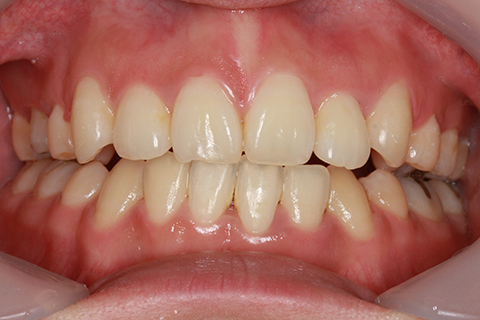

矯正期間18ヶ月

フルリンガル矯正2(上下の歯を舌側矯正で治療)

治療前

治療中

治療後

- 年齢・性別

- 42歳男性

- 治療期間

- 1年6ヶ月

- 抜歯

- なし

- 治療費

- 120万円(税込み)

- 備考

- マルチブラケットを用いた矯正治療

- 治療内容

- 反対咬合をフルリンガル矯正治療にて改善

- 施術の副作用(リスク)

- 表側矯正と比較して、歯根の角度を確立する「トルク」の力がかかりにくい。